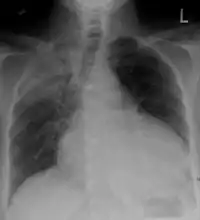

Chest x-ray: is non-specific and may not help identify a pericardial effusion but a very large, chronic effusion can present as "water-bottle sign" on an x-ray, which occurs when the cardiopericardial silhouette is enlarged and assumes the shape of a flask or water bottle.[2] Chest radiograph is also helpful in ruling out pneumothorax, pneumonia, and esophageal rupture.

A CT scan showing a pericardial effusion

A large anechoic (black) pericardial effusion as seen on ultrasound. Closed arrow: the heart, open arrow: the effusion- Pericardial effusion due to malignancy. Note bulbous heart and primary lung cancer in right upper lobe.